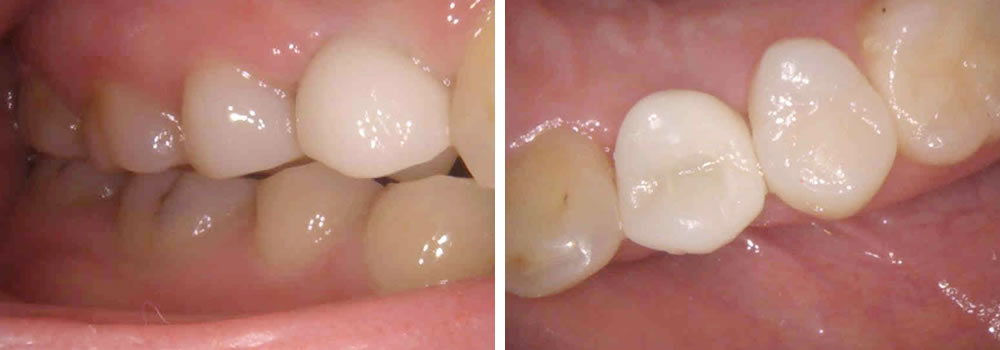

上部構造の装着・治療完了

インプラントと顎骨がきちんと結合していることを確認後、上部構造を装着して治療完了です。治療後は固いものも問題なく噛むことができ、何より見た目が普通の歯とほぼ変わらず、大変満足していただくことができました。